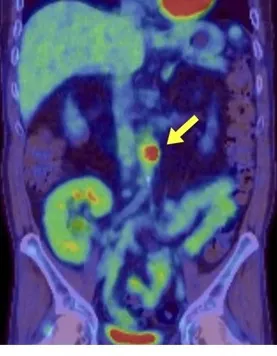

Foi iniciado tratamento com antibióticos intravenosos e realizada uma nefrostomia percutânea. A cultura da drenagem identificou o crescimento de Proteus mirabilis. Após avaliação com cintilografia, foi identificada a ausência de função renal no rim direito, levando à realização de uma nefrectomia.

Foi feito o diagnóstico de pielonefrite xantogranulomatosa.

A pielonefrite xantogranulomatosa, uma forma de pielonefrite crônica, está tipicamente associada à obstrução por cálculos e infecções recorrentes do trato urinário. As complicações podem incluir abscessos e fístulas. A perda da função renal é comum, e a nefrectomia é o tratamento definitivo. O paciente recebeu alta 5 dias após a cirurgia e apresentava-se bem, com função renal estável, após 1 mês de acompanhamento.